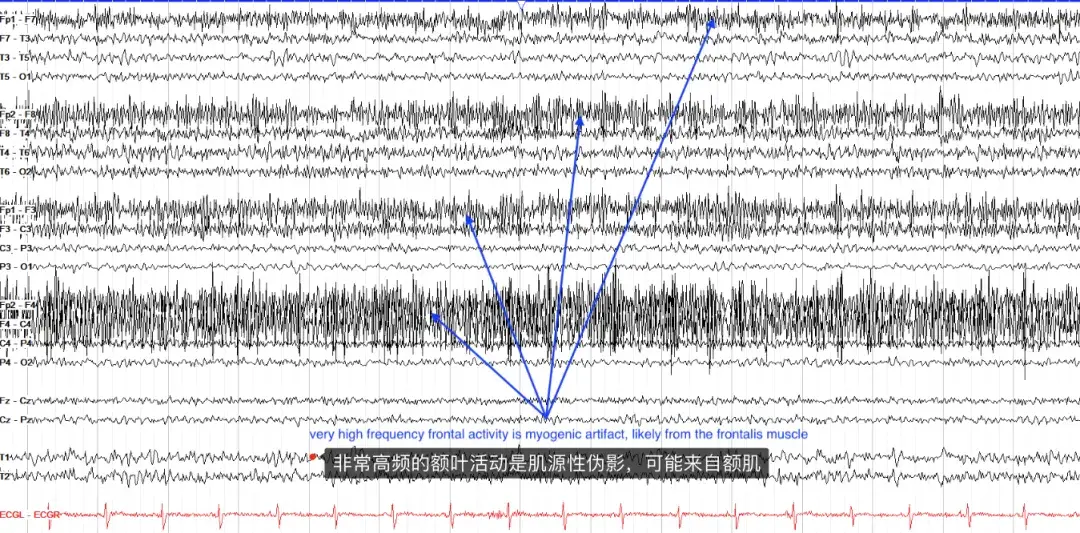

肌源性伪影来自肌肉运动,由于额肌和颞肌,最常见于额叶或外侧颞区。它的特点是覆盖正常大脑节律的高频率、通常低幅度的活动,并且通常在清醒状态下最为突出。值得注意的是,在顶点附近通常只有最小的肌源性伪影,所以如果看到那里有快速活动,就要怀疑一下产生的原因了。(但实际上,肌源性活动比头皮脑电图上的大脑活动要快得多)。